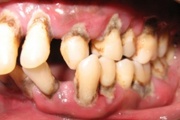

GAgP 25 aastasel suitsetaval puuduliku suuhügieeniga patsiendil